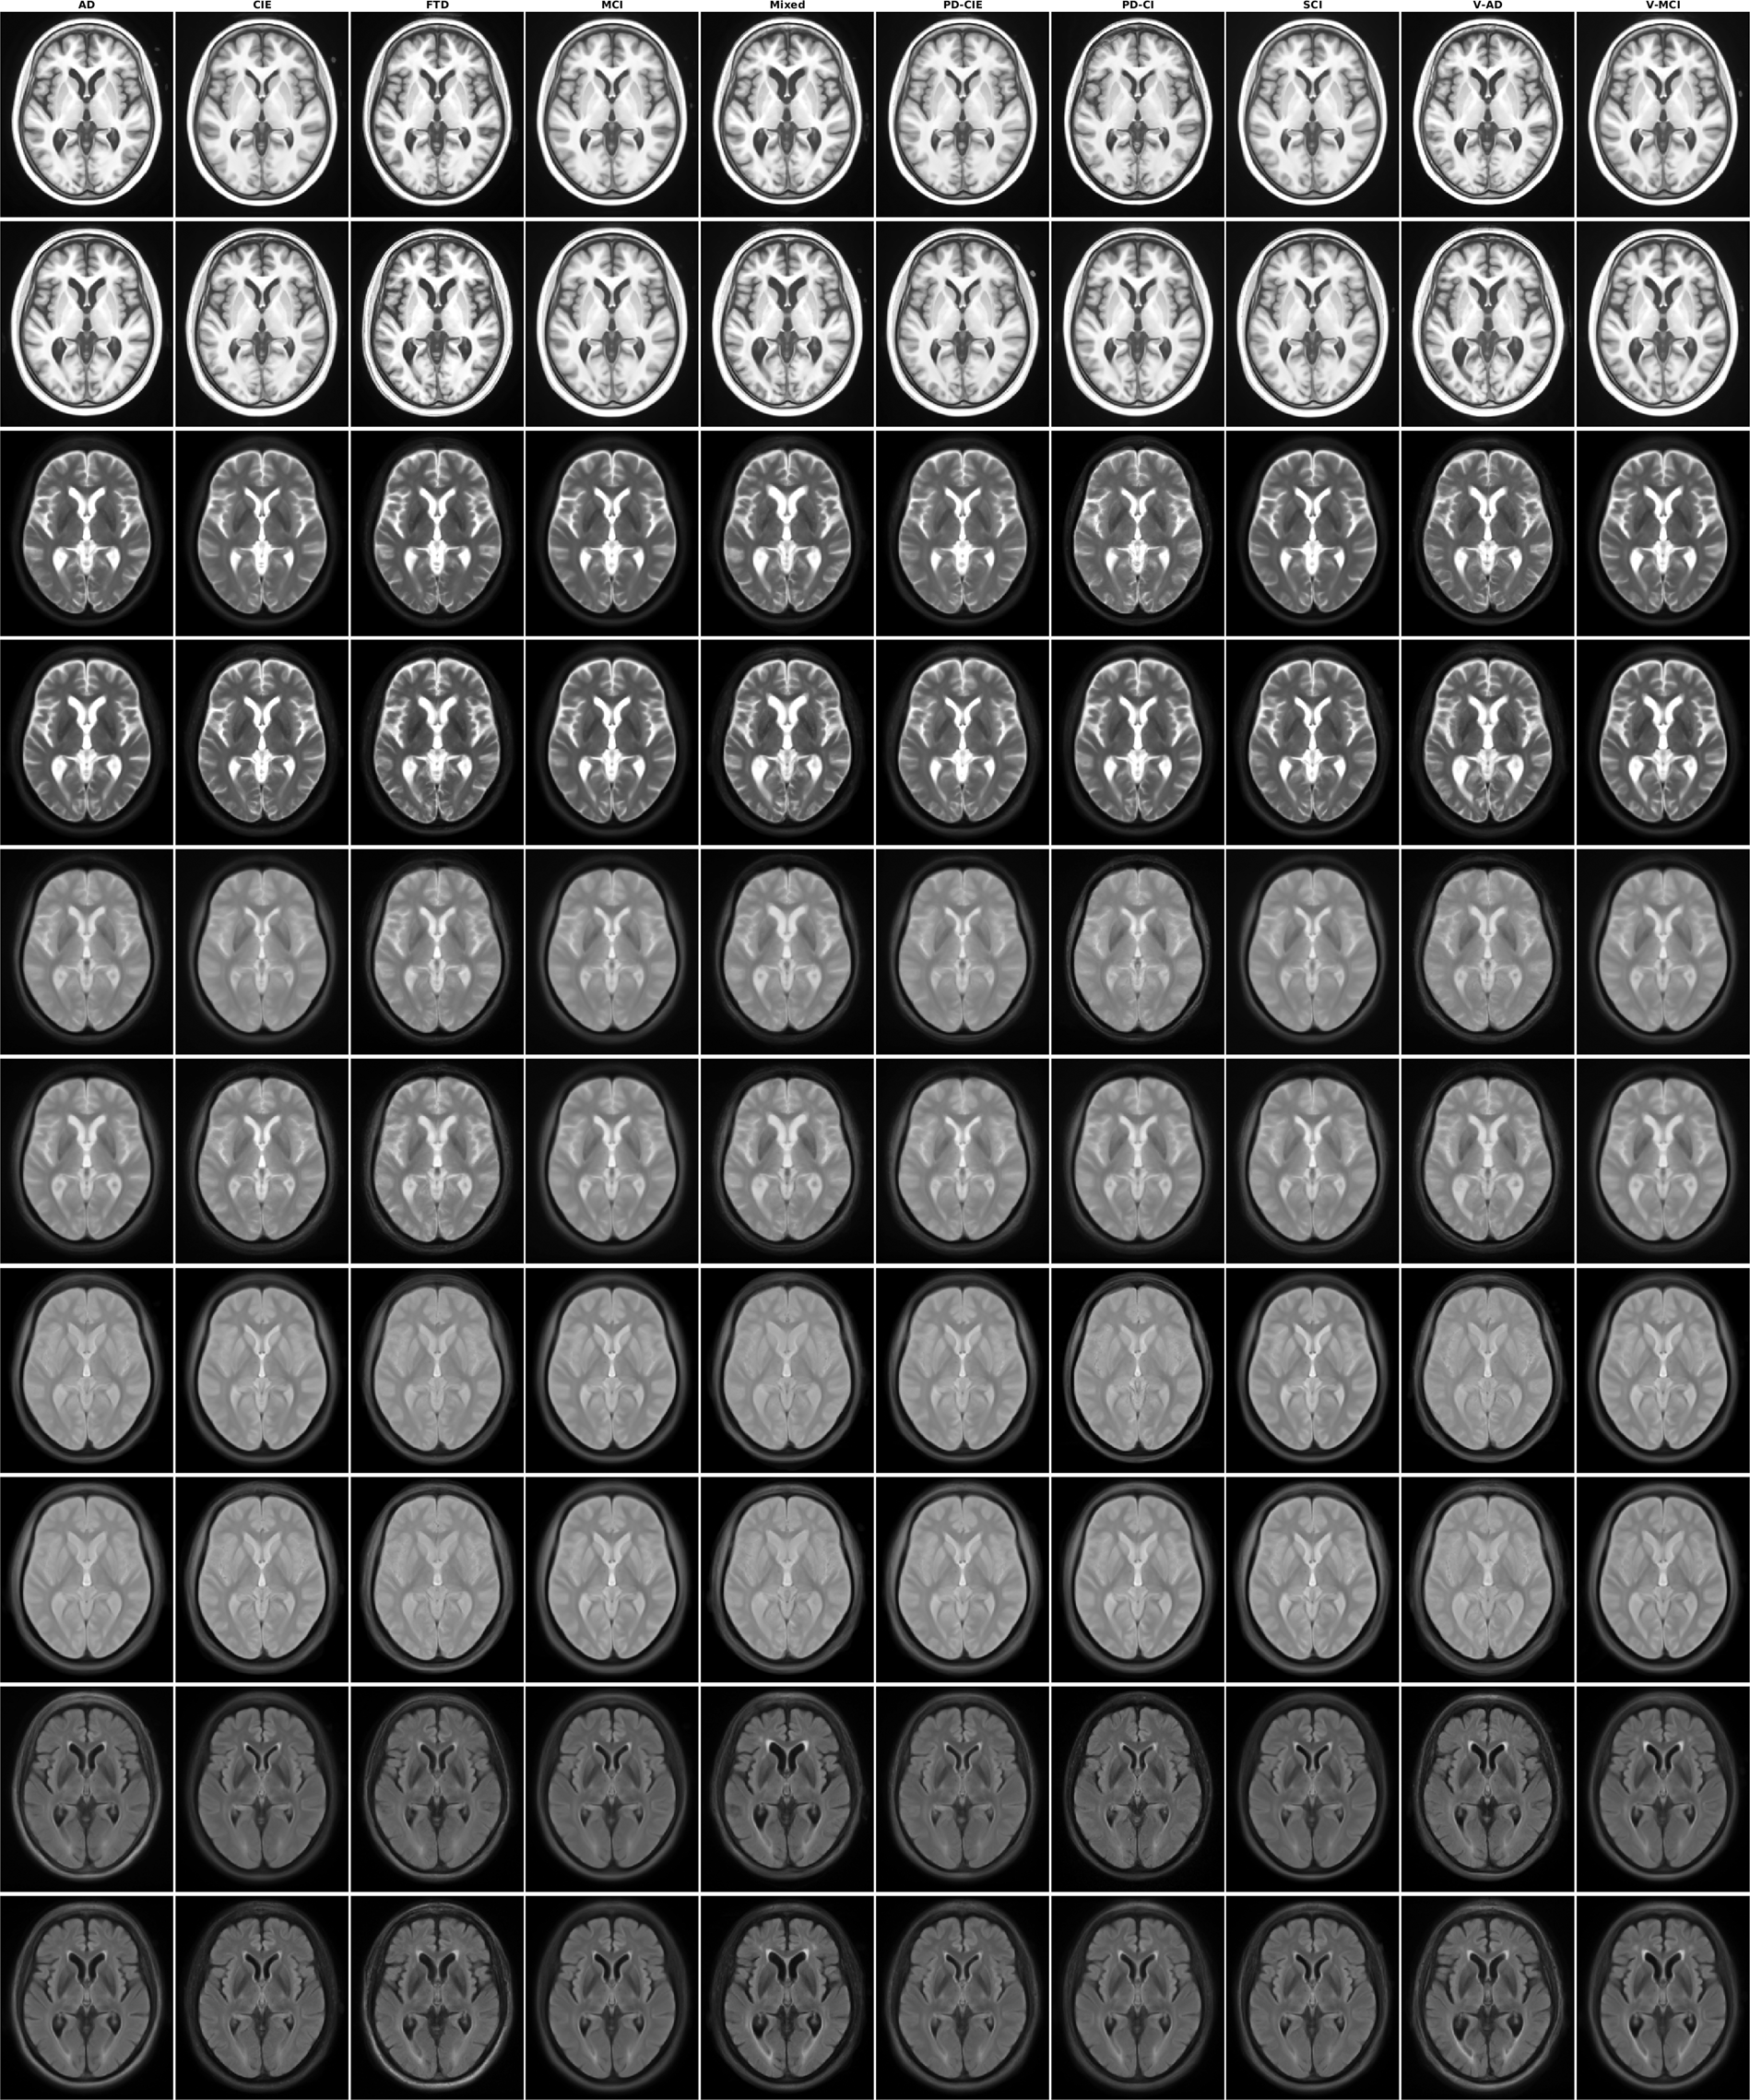

Fig. 6

Axial slices of average male and female templates for all sequences and diagnostic groups.